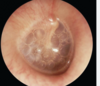

Otoscopic examination reveals **viscous bubbles behind the tympanic membrane** - what does this indicate? [1]

Glue ear / ottitis media with effusion